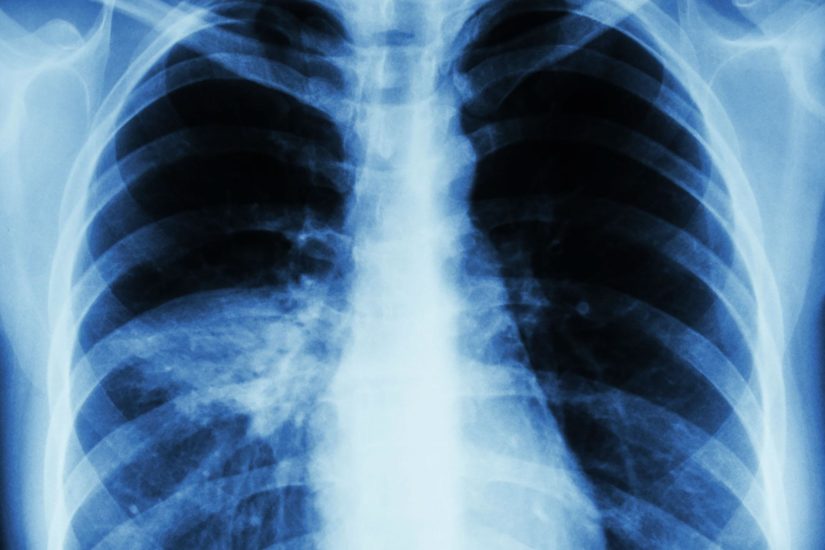

Αιτία θανάτου οι αναπνευστικές παθήσεις σε παγκόσμιο επίπεδο

Κατά τις τρεις τελευταίες δεκαετίες υπάρχει σημαντική αύξηση τόσο σε θανάτους όσο και σε αναπηρίες εξαιτίας των χρόνιων αναπνευστικών παθήσεων, σύμφωνα με μία νέα διεθνή επιστημονική μελέτη με επικεφαλής Κινέζους επιστήμονες, η οποία κάλυψε 195 χώρες. Οι συχνότερες παθήσεις των πνευμόνων είναι η Χρόνια Αποφρακτική Πνευμονοπάθεια (ΧΑΠ) και το άσθμα.

Οι ερευνητές, με επικεφαλής τον καθηγητή Μιν Σίε του Ιατρικού Κολλεγίου και του Νοσοκομείου Τονγκτζί του Πανεπιστημίου Επιστήμης και Τεχνολογίας Χουατζόνγκ στη Γουχάν (όπου και το επίκεντρο του νέου κοροναϊού), που έκαναν τη σχετική δημοσίευση στο βρετανικό ιατρικό περιοδικό BMJ (British Medical Journal), υπολόγισαν ότι ενώ το 1990 υπήρξαν 3,32 εκατομμύρια θάνατοι διεθνώς λόγω των χρόνιων αναπνευστικών παθήσεων, το 2017 είχαν αυξηθεί κατά 18% σε 3,91 εκατομμύρια.

Ο αριθμός των θανάτων αυξάνεται με την ηλικία διαχρονικά και εμφανίζει ιδιαίτερη αύξηση στα άτομα άνω των 70 ετών, μία τάση που αναμένεται να επιδεινωθεί, καθώς ο παγκόσμιος πληθυσμός γερνάει ολοένα περισσότερο. Το μεγαλύτερο πρόβλημα έχουν οι φτωχότερες χώρες, καθώς και γενικότερα οι άνθρωποι που ζουν οπουδήποτε σε συνθήκες στέρησης και κοινωνικής απομόνωσης.

Πέρα από τη γήρανση και την κοινωνικο-οικονομική κατάσταση, σοβαρός παράγοντας κινδύνου είναι  το κάπνισμα, η ρύπανση του αέρα και το μεγάλο σωματικό βάρος. Το κάπνισμα είναι η κυριότερη αιτία θανάτου και αναπηρίας λόγω ΧΑΠ και άσθματος (1,4 εκατομμύρια θάνατοι το 2017) και ακολουθεί η ατμοσφαιρική ρύπανση για θανατηφόρα Χρόνια Αποφρακτική Πνευμονοπάθεια.